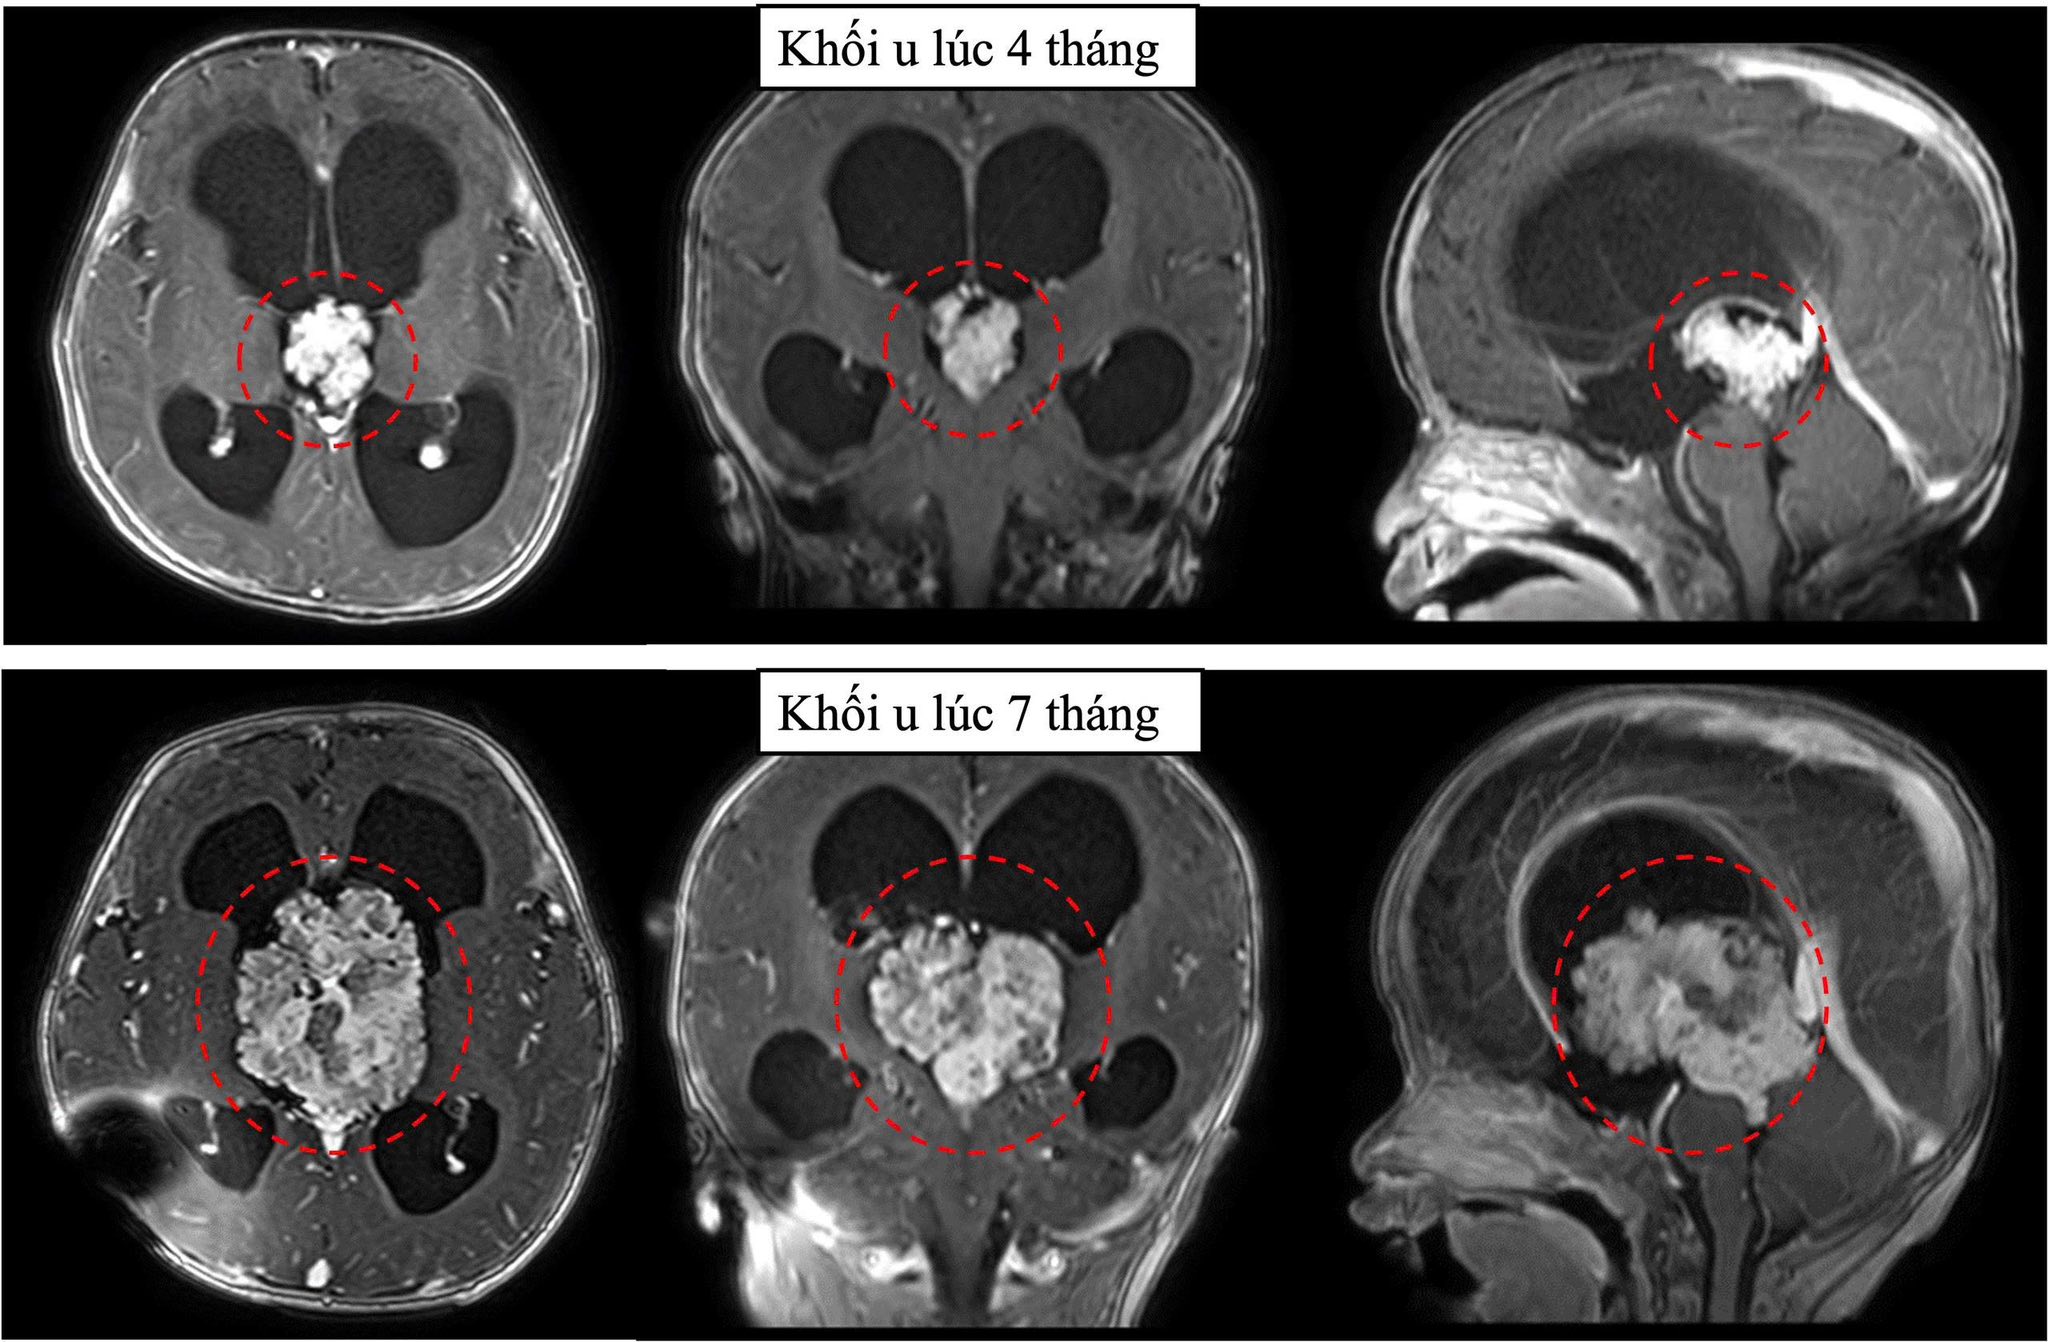

Ảnh chụp phim cho thấy u não phát triển rất nhanh, tăng kích thước hơn gấp 3 lần sau 3 tháng. Ảnh: BVCC

Hình ảnh cộng hưởng từ sọ não ghi nhận khối u vùng não thất 3 gây chèn ép dẫn đến não úng thủy tắc nghẽn. Khối u nằm vị trí não thất 3, vị trí sâu với nhiều cấu trúc thần kinh quan trọng xung quanh, là một trong những vị trí can thiệp rất khó trong phẫu thuật sọ não.

Tuy nhiên, phim cộng hưởng từ sọ não 3 tháng sau cho thấy u não phát triển rất nhanh, tăng kích thước gấp 3 lần. Không thể trì hoãn thêm, bác sĩ khoa Ngoại thần kinh đã tư vấn gia đình phẫu thuật mổ lấy u để kịp thời cứu bệnh nhi.